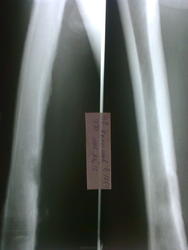

Здравствуйте, коллеги. Помогите с диагностикой. Больной 1954 г.р. пришел от врача-терапевта с направлением "остеоартроз левого коленного сустава", жалуется на боли, со слов год назад получил травму. Профессия-пастух.

Периостит однозначно есть, а вот разреженность костной ткани в н/3 бедренной  кости мне непонятно. Добавил с архива 2 флюорограммы и сделали Р-гр правой бедренной кости

Имеется поражение всего медадиафиза бедренной кости с переоссальными наслоениями, утолщение кортикального слоя. Наличие очага деструкции в н\3 бедренной кости без четкого контура с наличием остесклеротического вала. По моему увеличение плотности мягких тканей. Округлый дефект? в проекции межмыщелкового возвышения б\б коости с зоной остеосклероза. Первично хронический остеомиелит б\б кости?

Саркома Юинга?surprise  Никогда не видела, но бльше ничего в голову не приходит...

Мне тоже кажется нечто злокачественное в данном снимке

На Педжета не похоже?

По-моему что-то системное - периост реагирует на большом протяжении, но непосредственно в месте разрежения костной ткани этого нет. Да и возраст не в пользу опухоли..

Периостоз похож на Бамбергера-Мари, но остеолизиз здесь не укладывается. На фиброзно-кортикальный дефект не очень тянет (хотя в много ходящего пешком пастуха может быть). Остеолитические метастазы, скорее. Полный онкопоиск. РГ ОГК обязательно.